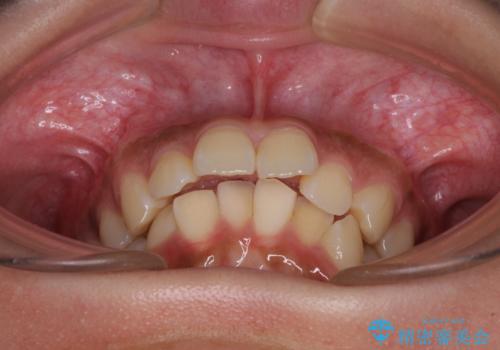

- 下唇に上顎前歯の跡がつくくらいに突出した前歯とデコボコを気にして来院された患者様です。

口元の突出感改善のため、上下左右の第一小臼歯4本を抜歯し、ワイヤー装置にて矯正治療を行うこととしました。

それほど口元の突出感が強いわけではありませんでしたが、下唇に前歯引っかかる感触が気になっていたため、抜歯矯正を行うこととしました。